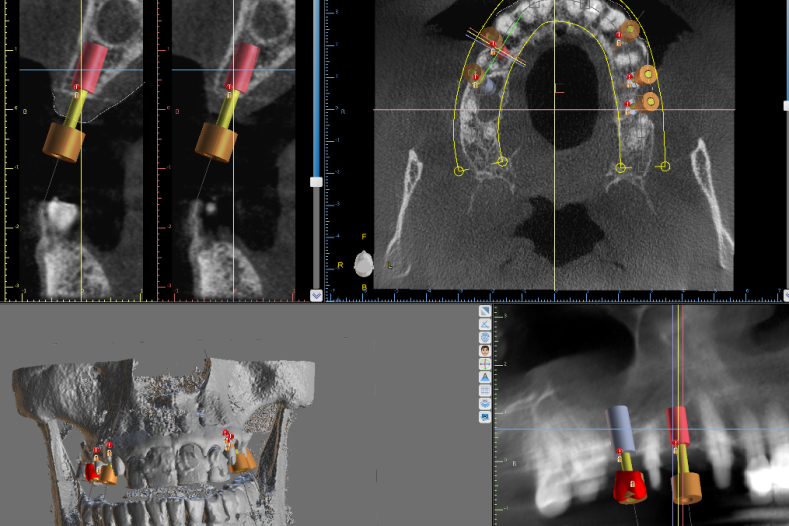

Zahnimplantat

Zahnwurzeln können festsitzend mittels Implantaten ersetzt werden.